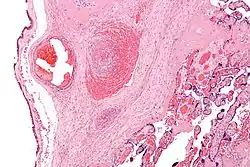

![]() | |

| A child with cerebral palsy being assessed by a physician | |